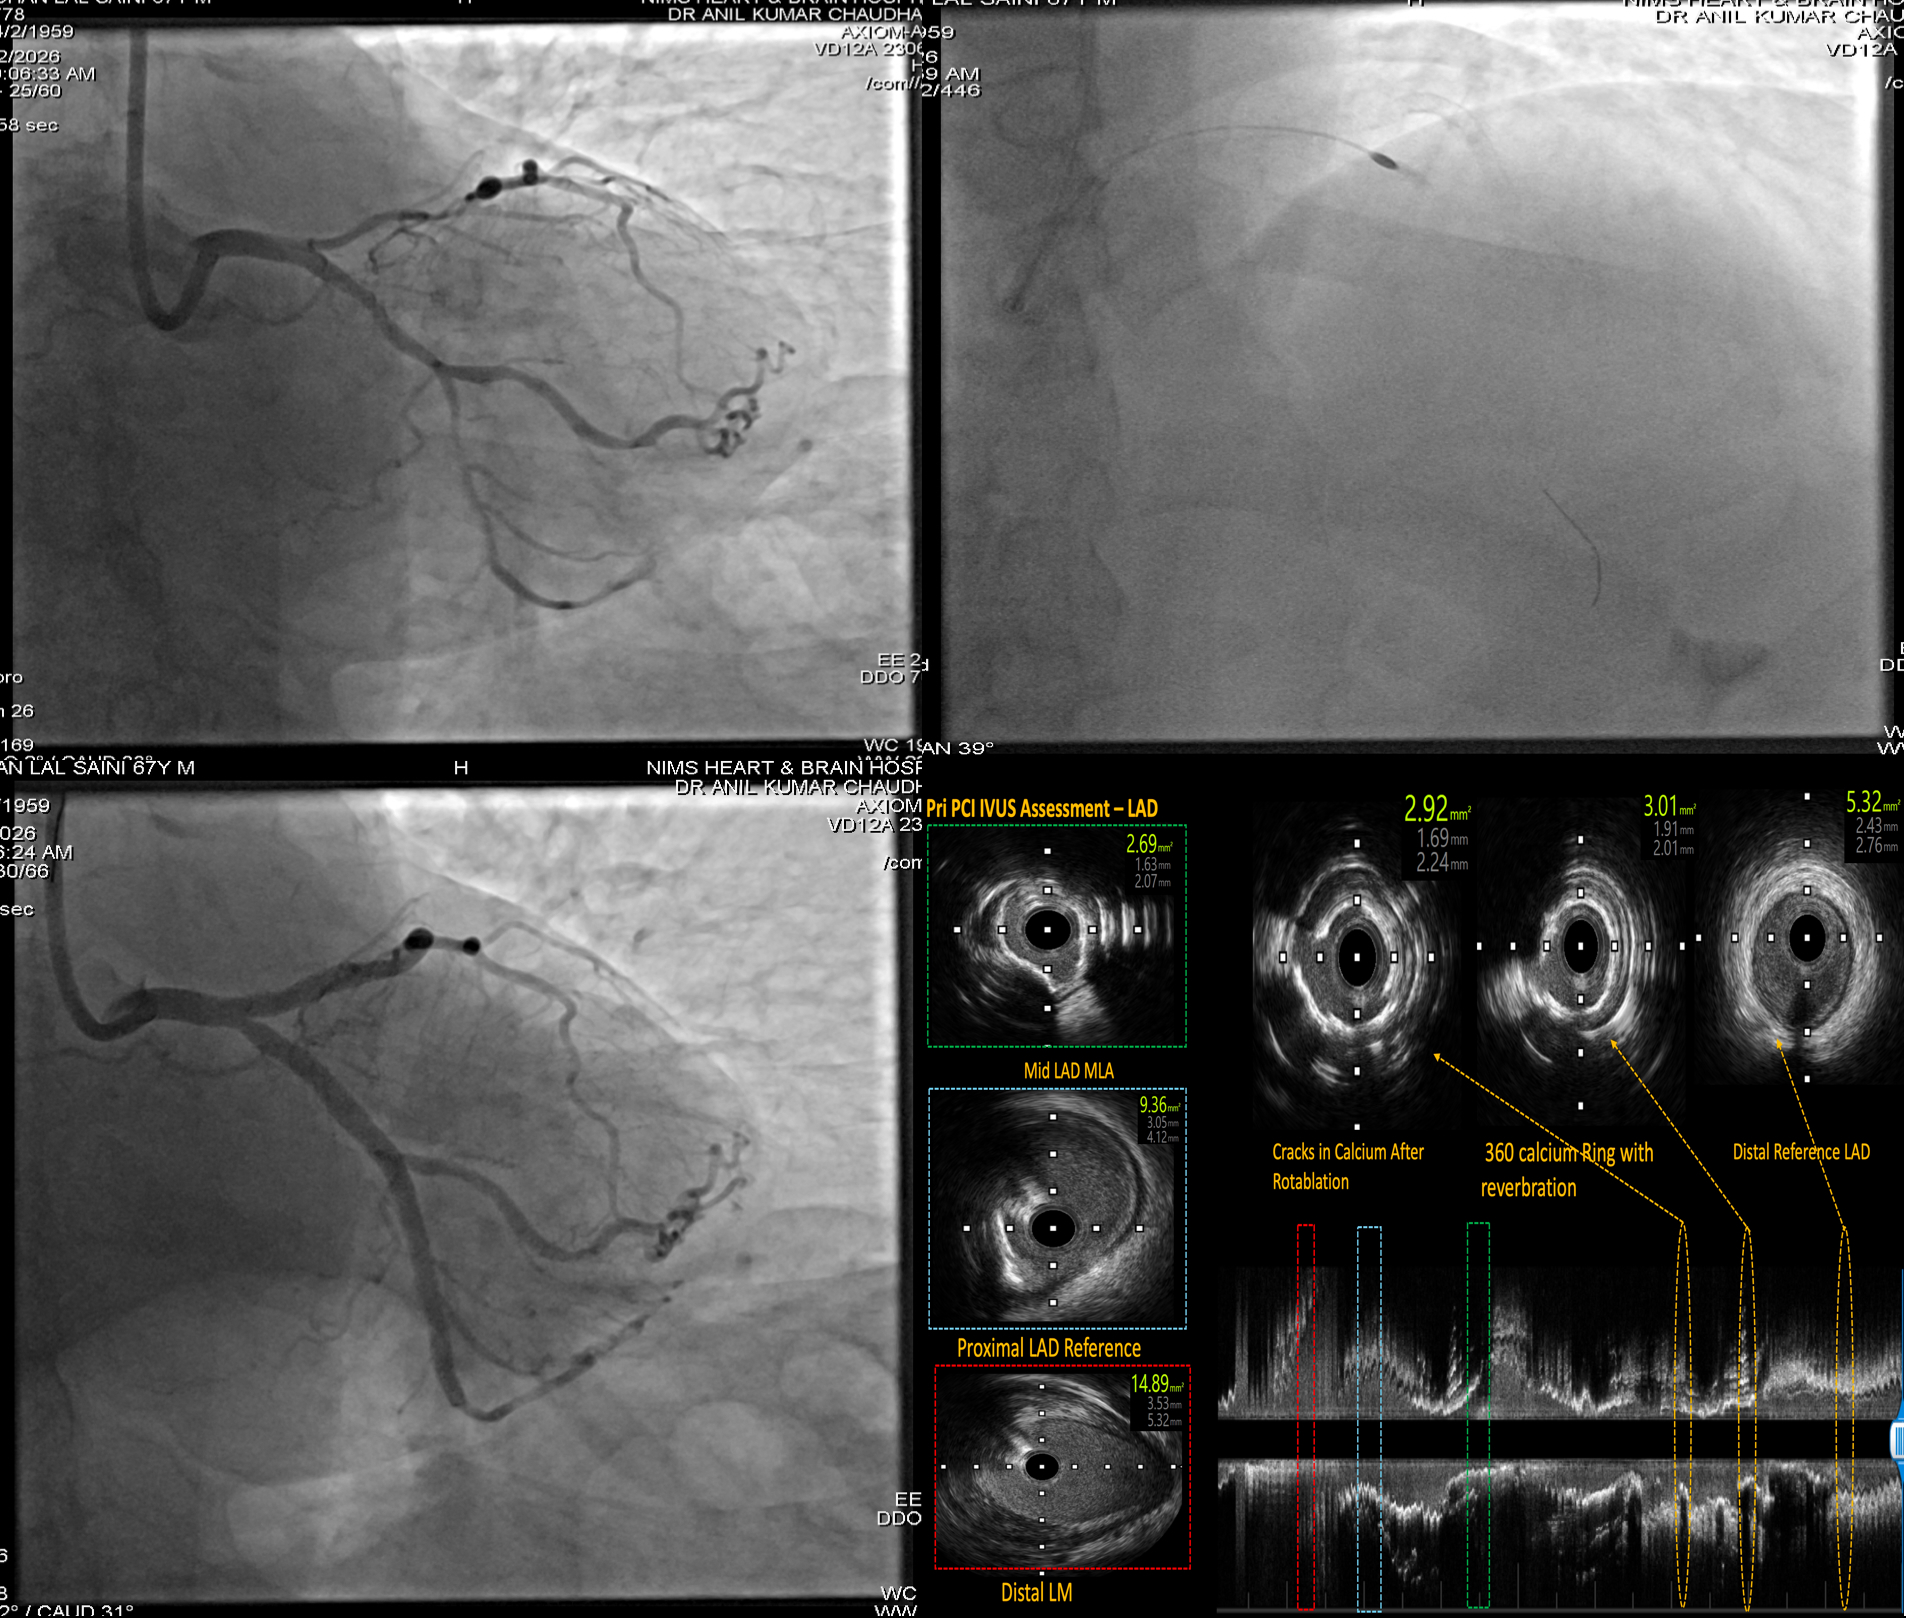

Complex Coronary Angiography in Jaipur – Dr. Anil Kumar Choudhary If you're suffering from chest pain, breathlessness, or have been diagnosed with multiple or difficult heart blockages, Complex Coronary Angiography is the first and most crucial step in your treatment journey. Dr. Anil Kumar Choudhary, the best interventional cardiologist in Jaipur, offers expert-level precision in performing this life-saving diagnostic procedure. With vast experience in advanced cardiac imaging and diagnosis, Dr. Choudhary provides highly accurate and detailed coronary assessments, especially in patients with multiple blockages, previous bypass surgeries, diabetes, or high-risk profiles. 🩺 What is Complex Coronary Angiography? Coronary Angiography is a diagnostic procedure that uses a special contrast dye and X-ray imaging to visualize the arteries supplying blood to your heart. In complex cases, this procedure is performed with advanced imaging techniques and requires high-level expertise to interpret intricate blockages or anomalies. Complex Coronary Angiography is typically needed when: There is suspected multi-vessel disease The patient has chronic total occlusions (CTOs) There’s history of previous stents or bypass surgery (CABG) The patient has diabetes, kidney disease, or low ejection fraction (LVEF) Symptoms are unusual, prolonged, or high risk 🔬 Dr. Anil Kumar Choudhary’s Expertise in Complex Angiography Dr. Choudhary is known for his high diagnostic accuracy and sharp interpretation of even the most challenging coronary cases. His use of intravascular imaging tools such as: IVUS (Intravascular Ultrasound) OCT (Optical Coherence Tomography) FFR (Fractional Flow Reserve) ensures detailed visualization and functional analysis of blockages. This level of precision helps in planning the most appropriate and safe intervention, whether it be angioplasty, stenting, or surgery. 💡 Benefits of Choosing Dr. Anil Kumar Choudhary for Complex Coronary Angiography 🏥 Advanced Cath Lab with high-resolution imaging systems 🎓 Expert in diagnosing complex coronary artery disease (CAD) 🧠 Deep understanding of hemodynamics and coronary physiology 💯 Helps avoid unnecessary stenting through accurate lesion assessment 🩺 Specialist in post-bypass and restenosis case evaluation ✅ When is Complex Coronary Angiography Recommended? Recurrent chest pain or angina despite medication Suspicion of triple vessel disease or left main artery blockage Previous CABG (bypass surgery) or angioplasty patients Cases with diabetes, chronic kidney disease, or heart failure Prior equivocal stress test or CT angiography results Evaluation of in-stent restenosis or stent failure ❤️ Why Dr. Anil Kumar Choudhary is the Best Cardiologist for Complex Angiography in Jaipur 👨‍⚕️ Over a decade of interventional cardiology experience 💻 Use of cutting-edge technology and imaging tools 🧪 Expertise in high-risk and redo cases 🤝 Patient-centric care with ethical and transparent consultation 📈 High diagnostic precision ensuring targeted treatment planning 📍 Visit Jaipur’s Best Coronary Angiography Specialist Today Don't leave your heart health to chance. If you or your loved one has symptoms of serious heart disease or complex cardiac history, trust Dr. Anil Kumar Choudhary, the most reliable name for complex coronary angiography in Jaipur.

Complex Coronary Angioplasty in Jaipur – Dr. Anil Kumar Choudhary When it comes to advanced and life-saving cardiac interventions, Dr. Anil Kumar Choudhary is widely recognized as the best interventional cardiologist in Jaipur, known for his exceptional skill in performing Complex Coronary Angioplasty. Specializing in treating high-risk and difficult coronary blockages, Dr. Choudhary delivers world-class results using the latest technology and techniques. ❤️ What is Complex Coronary Angioplasty? Complex Coronary Angioplasty (also known as PCI – Percutaneous Coronary Intervention) refers to advanced angioplasty procedures used to treat challenging coronary artery blockages. These may include: Chronic Total Occlusions (CTOs) Left Main Coronary Artery Disease Severe Multivessel Coronary Artery Disease Calcified Arteries Bifurcation Lesions Restenosis (re-blockage after stenting) Unlike routine angioplasty, these cases demand high expertise, specialized tools (like rotablation, IVUS, OCT), and a deep understanding of coronary anatomy and hemodynamics. 🏥 Dr. Anil Kumar Choudhary’s Expertise in Complex PCI With a reputation for excellence in interventional cardiology, Dr. Anil Kumar Choudhary has handled some of the most complex coronary cases with successful outcomes. His approach combines: Precision and safety Use of advanced imaging (IVUS/OCT) for lesion assessment Rotablation & atherectomy for hard, calcified plaques Bifurcation and multivessel stenting techniques Experience in left main coronary angioplasty 🚨 When is Complex Angioplasty Recommended? Dr. Choudhary may suggest complex angioplasty in cases such as: Patient is not suitable for bypass surgery (CABG) High-risk or elderly patients with multiple blockages Blockages in critical arteries like the left main artery Patients with diabetes or weak heart function (low ejection fraction) Previously failed angioplasty or re-narrowing of stents 🔬 Advanced Tools & Techniques Used by Dr. Choudhary IVUS (Intravascular Ultrasound) – for accurate visualization inside arteries OCT (Optical Coherence Tomography) – to guide precise stent placement Rotablation – for drilling hard, calcified plaques Dual-stenting techniques – for complex bifurcation lesions Drug-eluting stents (DES) – to reduce re-blockage risk ✅ Why Choose Dr. Anil Kumar Choudhary for Complex Coronary Angioplasty in Jaipur? 🩺 Over a decade of experience in complex and high-risk PCI 🏥 Advanced Cath Lab with cutting-edge imaging tools 💯 High success rate in critical cases 👨‍⚕️ Personalized treatment planning and post-procedure care 💬 Transparent patient communication and ethical practice Recognized as the best cardiologist in Jaipur for complex interventions ❤️ Conditions Treated with Complex Angioplasty Chronic Total Occlusion (CTO) Triple Vessel Disease Left Main Coronary Artery Blockage Coronary Artery Calcification Bifurcation and Trifurcation Lesions Stent Restenosis Low LVEF with CAD Unstable Angina or Heart Attack 📍 Visit the Best Heart Specialist in Jaipur for Complex Coronary Care If you've been advised bypass surgery or have been diagnosed with multiple or complex blockages, consult Dr. Anil Kumar Choudhary for a second opinion. Many patients have avoided open-heart surgery through his expert complex angioplasty.